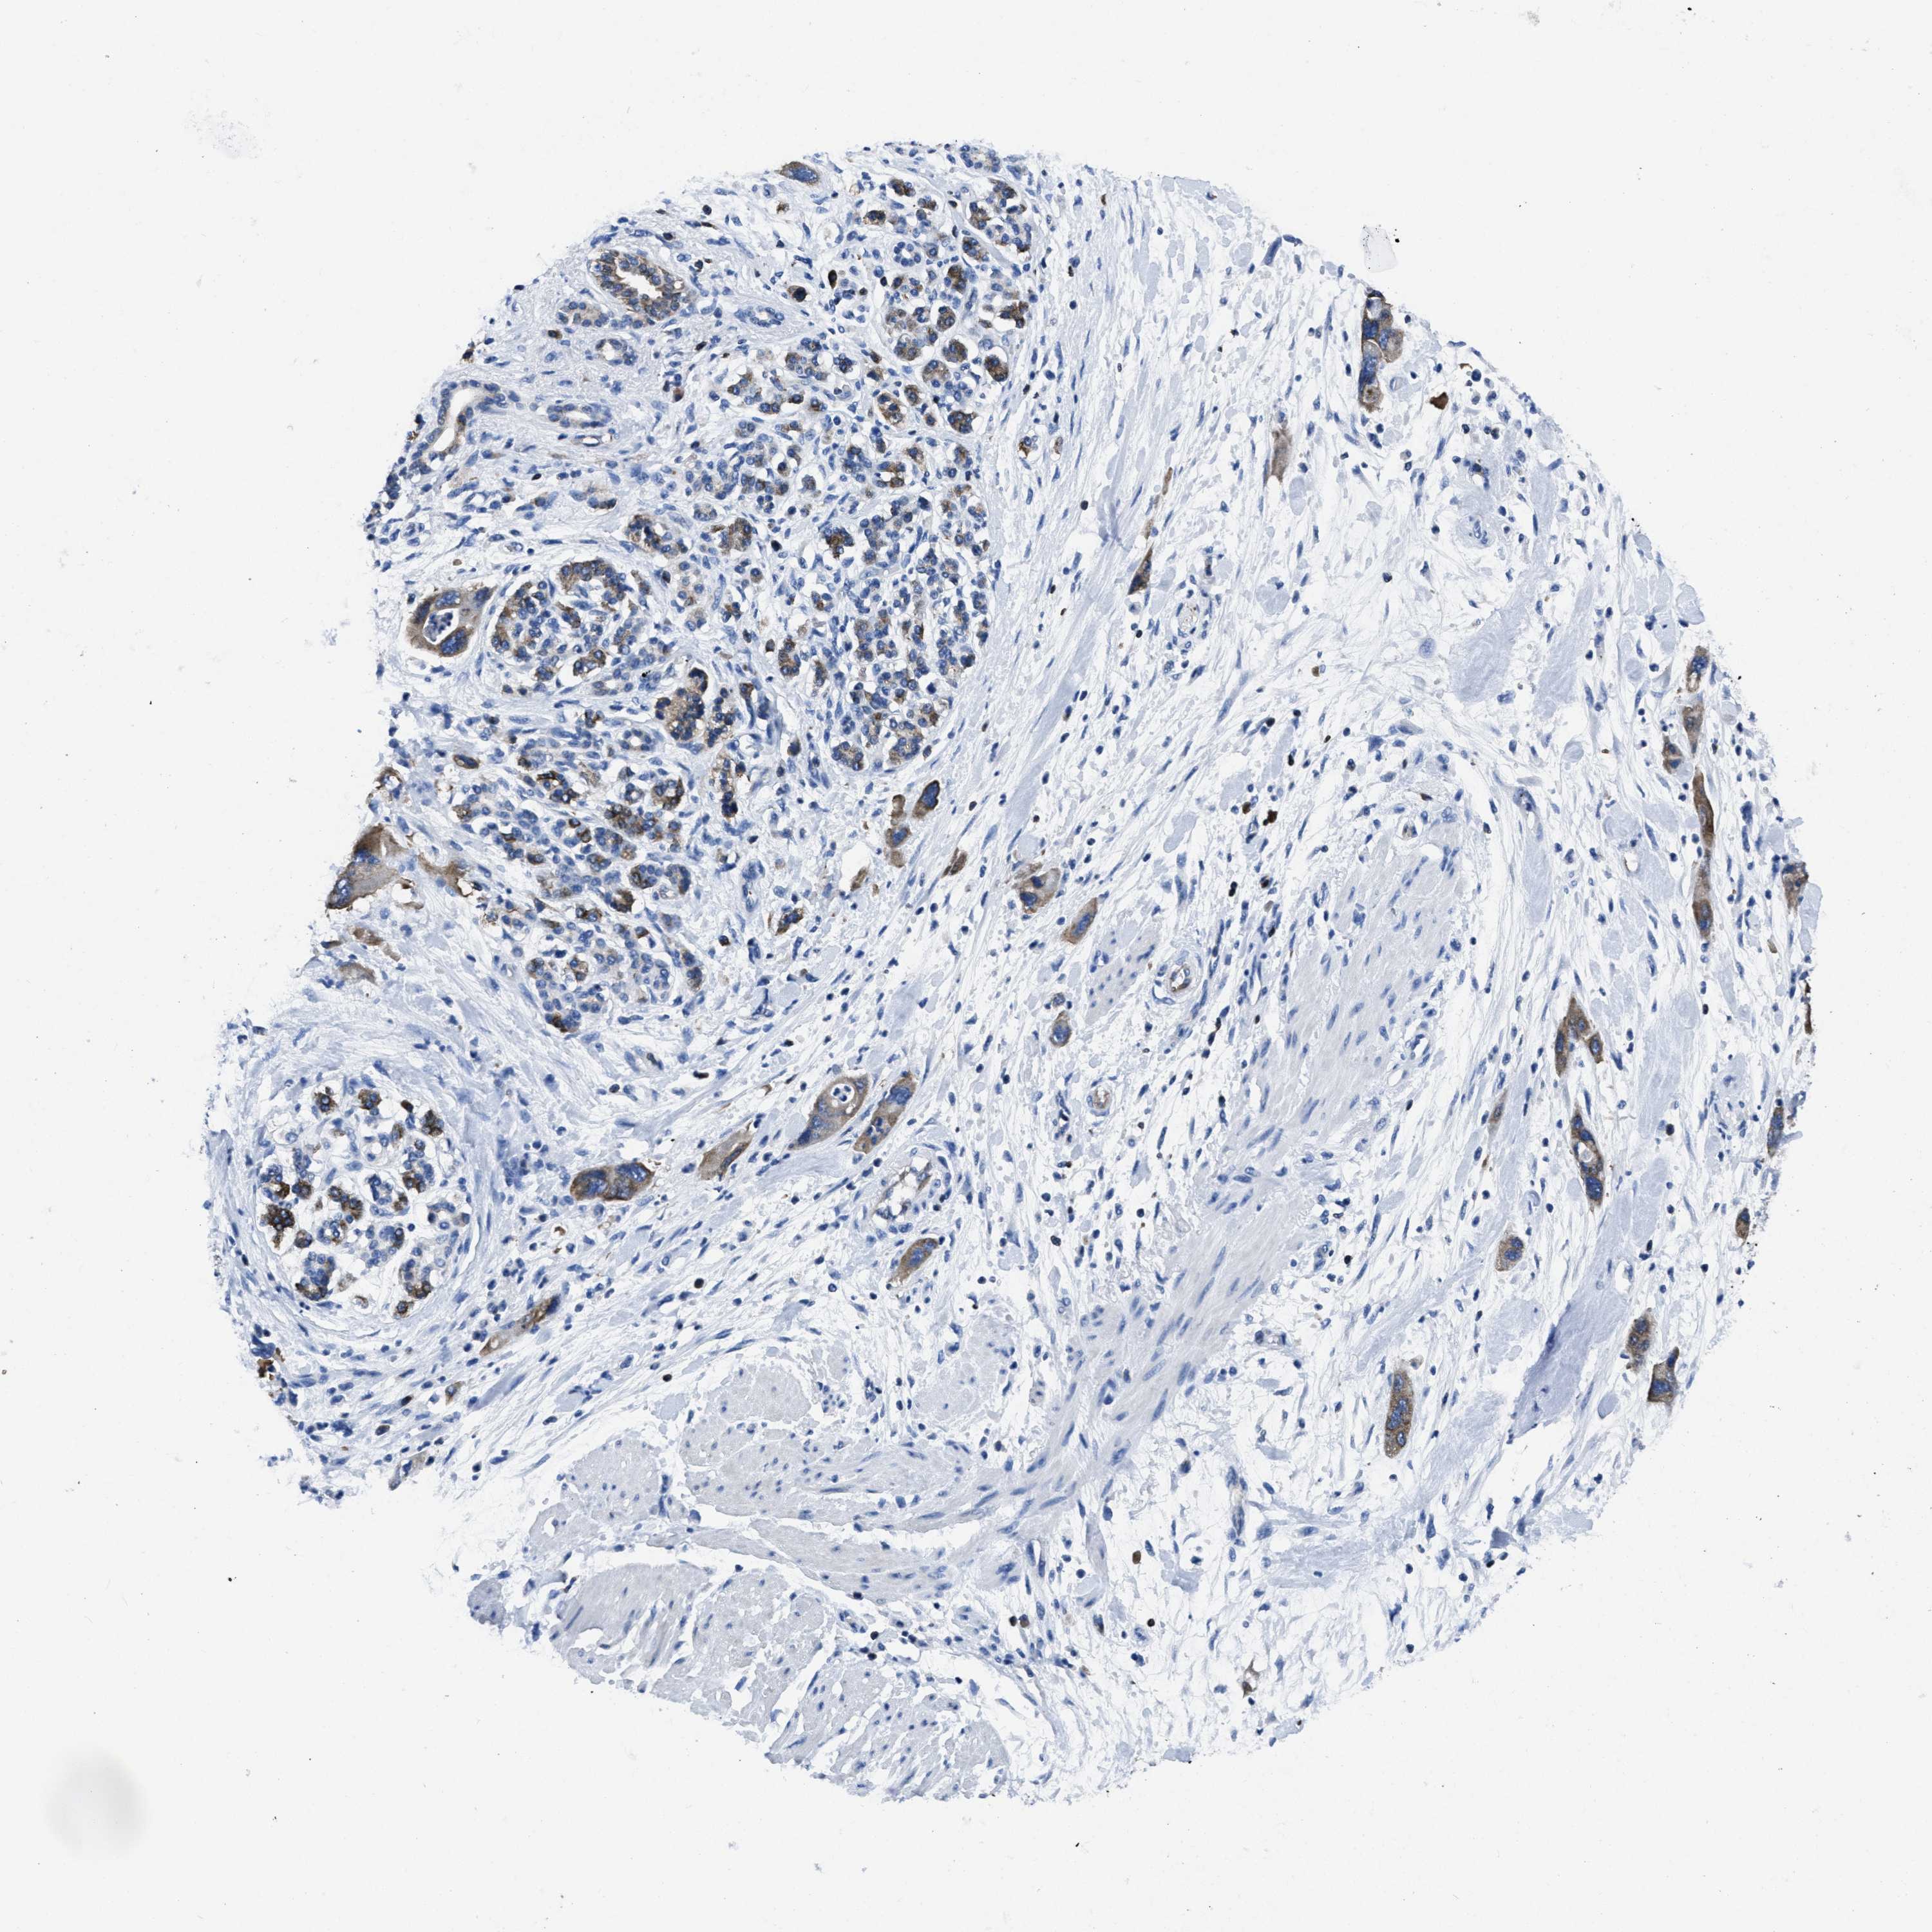

PANCREATIC CANCER - Protein expressioni

A mouse-over function shows sample information and annotation data. Click on an image to view it in a full screen mode. Samples can be filtered based on level of antibody staining by selecting one or several of the following categories: high, medium, low and not detected. The assay and annotation is described here.

Note that samples used for immunohistochemistry by the Human Protein Atlas do not correspond to samples in the TCGA dataset.

Antibody stainingi

Antibody staining in the annotated cell types in the current human tissue is reported as not detected, low, medium, or high, based on conventional immunohistochemistry profiling in selected tissues. This score is based on the combination of the staining intensity and fraction of stained cells.

Each image is clickable and will lead to virtual microscopy that enables deeper exploration of all samples and also displays staining intensity scores, fraction scores and subcellular localization as well as patient and tissue information for each sample.

Antibody HPA008572

Antibody CAB018594

Staining

High

Medium

Low

Not detected

Intensity

Strong

Moderate

Weak

Negative

Quantity

>75%

75%-25%

<25%

None

Location

Nuclear

Cytoplasmic/membranous

Cytoplasmic/membranous,nuclear

Adenocarcinoma, NOS